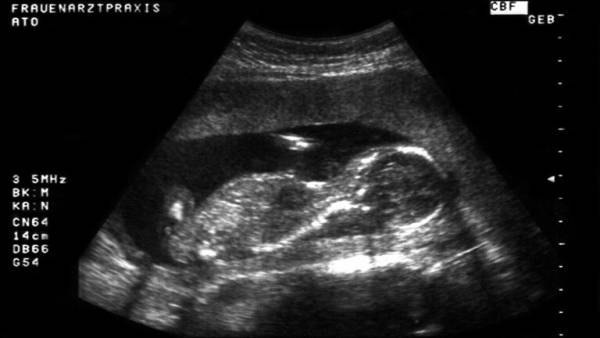

وضع رجل متحول جنسيا مولودا، بعد حصوله على حيوانات منوية من متبرعة أنثى متحولة جنسيا في بريطانيا، بعد توصيات الأطباء بإمكانية حدوث ذلك.

وكان الأطباء قد نصحوا روبن شارب، 39 عاما، بإمكانية حمله، لأنه لا زال يحمل رحما ومبيضين، حيث تحول إلى رجل قبل 12 عاما، وتعاطى الهرمونات التي ساعدته في نمو شعر الوجه وخشونة صوته، وإضفاء ملامح ذكورية على شكله.

وبدأ الشريكان عملية محاولة الإنجاب، بمراقبة هرمونات ومستوى خصوبة شارب، وعلى الرغم من أن إحدى الصديقات عرضت حمل الطفل إذا لزم الأمر، إلا أن شارب رأى أن يحمل الطفل بنفسه. قائلا: "لقد استيقظت صباح اليوم التالي، وبدأت الدورة الشهرية للمرة الأولى منذ 6 سنوات، كان ذلك بمثابة ارتياح شديد بالنسبة لي، حيث يعني إمكانية عملية التخصيب بالتلقيح داخل الرحم".

وافقت المتبرعة، وبدأوا رحلة علاج الخصوبة التي تكلف 7860 دولارا لثلاث دورات من العلاج، لم تنجح الأولى، لأن حقنة الخصوبة التي حصلت عليها شارب، جعلت جسمه يفرز 6 بويضات، ما يعني إمكانية أن يحمل بـ 6 أطفال!

ومع تقليص العدد تمكن شارب من الحصول على جنين، ووضع شارب طفله عن طريق الولادة القيصرية، ومعلقا على التجربة قال روبن شارب: "لقد استغرق الأمر 6 سنوات للوصول إلى هذه النتيجة، ولكن لدي الآن طفل وهو هدفي الأساسي. الآن أحس أنني قد اكتملت".